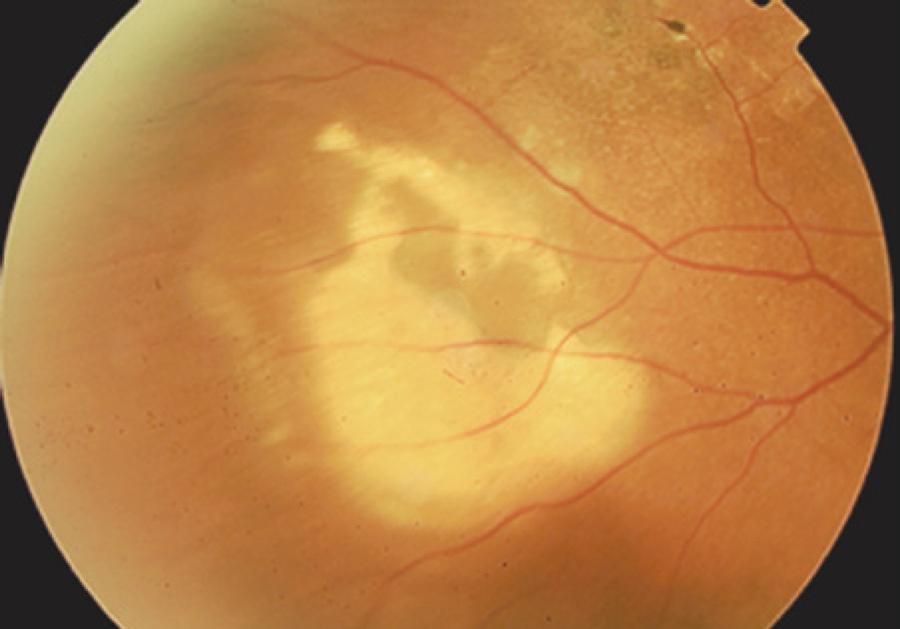

Upon initial examination, the patient’s visual acuity was 20/20 in both eyes, she had no afferent pupillary defects, and had normal intraocular pressure measurements. Slit-lamp examination revealed only pinguecula on the right eye (OD) and asteroid hyalosis in the left eye (OS). Upon fundus examination of OD, there was an elevated lesion in the middle periphery of the inferior temporal region adjacent to multiple areas of pigment epithelium detachment (PED). In addition, at 2 o'clock in relation to the lesion, a peculiar, smaller elevation resembling a vascular tumor (Figure 1A) was observed.

Figure 1. A) Fundus retinography demonstrating an elevated lesion in the mid-periphery of the inferior temporal vascular arcade, as shown by the long black arrow, and a lesion resembling the vascular tumor at the 2 o'clock position, as shown by the short black arrow. B) Right fundus. A middle phase of the fluorescein angiography showing minimal leakage and pooling. C) Indocyanine green angiogram showing the tubular elements ending in aneurysmal or polypoidal dilatations with little leakage of the dye. In both exams, the lack of fluorescence (i.e., black appearance) was due to major hemorrhagic pigment epithelium detachment.

The OCT examination of the major lesion in OD revealed a large PED with adjacent smaller lesions resembling a vascular tumor, and these observations were correlated with retinal serous detachment (Figure 2). Fluorescein angiography of OD showed a patchy area of subretinal staining of undetermined origin, with minimal leakage and a blockage area corresponding to the elevated lesion (Figure 1B). ICG revealed the presence of an inner choroidal vascular abnormality that ended in multiple small, hyperfluorescent polyps with leakage characteristic of IPCV, as well as a permanent blockage area observed during all phases of the angiogram, which corresponded to the major PED (Figure 1C). No macular changes were observed. One year later, there was decreased dimension and discoloration of the lesions, which now resembled a choroidal osteoma (Figure 3). After the initial visit no treatment was administered, because the macula was not threatened.

A major strength of this case, which we followed for one year, was that the differential diagnosis performed early after disease onset included vasoproliferative acquired disease, capillary hemangioma, focal posterior scleritis, and primary tumor. However, in the late phase (Figure 3), due to the appearance of discolored lesions likely associated with the absorption of blood, potential diagnoses suggested were metastatic tumors and choroidal osteoma.